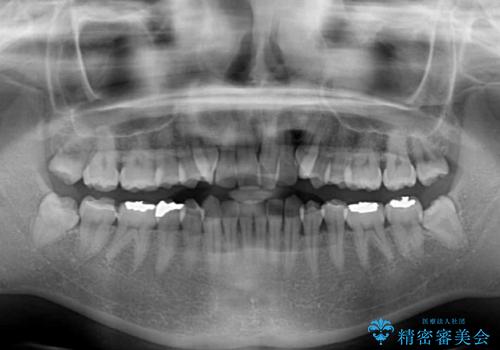

八重歯を改善 ワイヤー装置での抜歯矯正

- 目立つ八重歯を気にして来院された患者様です。

下顎歯列の叢生は軽度であることと、口元の突出感が全くなかったことから、八重歯解消のために上顎左右第一小臼歯を抜歯し、ワイヤー装置にて矯正治療を行うこととしました。